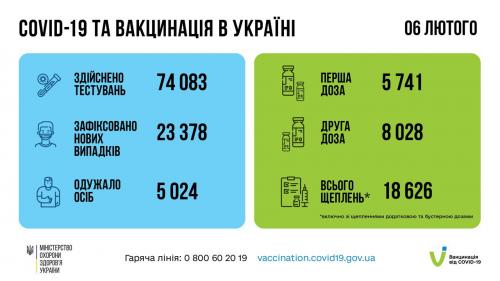

В Україні людям, які отримали бустерну дозу, даруватимуть знижку на поїздку в таксі